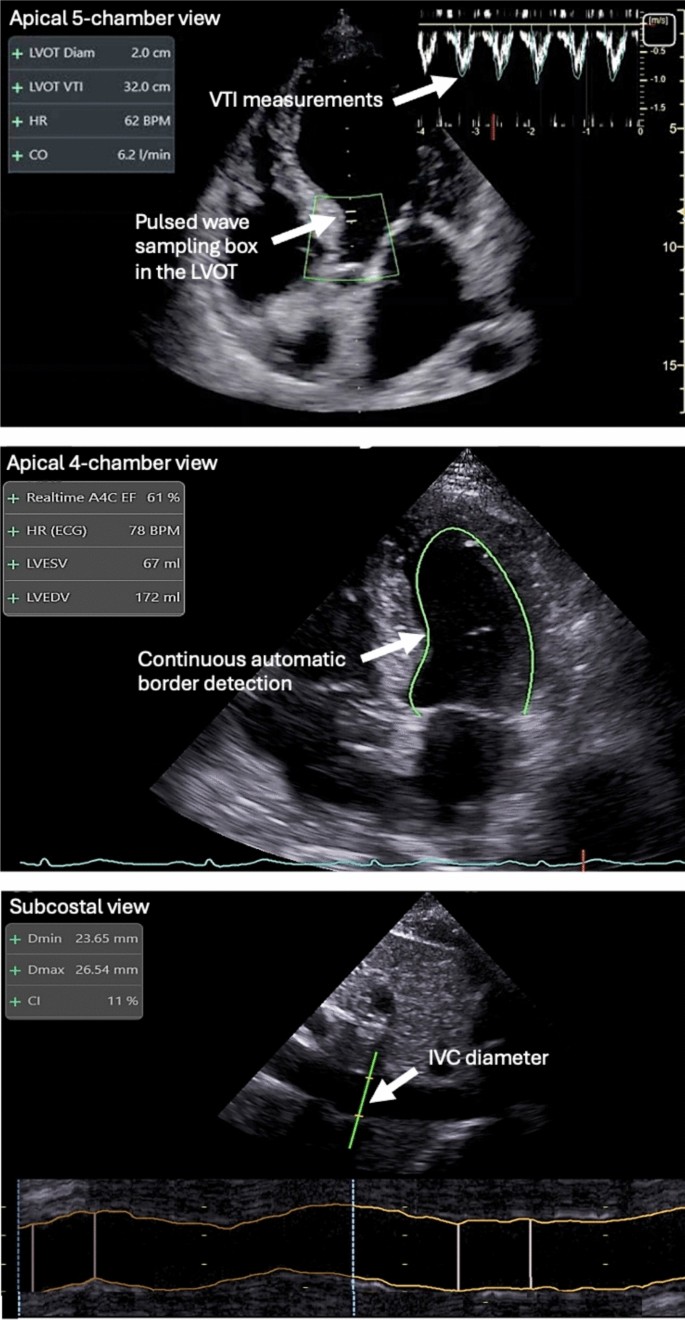

Annals of Intensive Care

The Ultrasound Journal